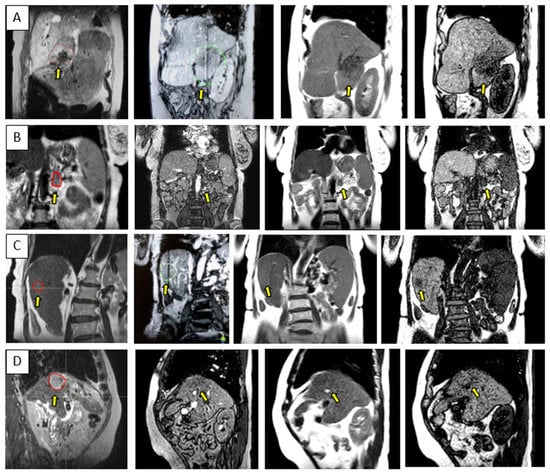

Figure 3 and Figure 4 show the comparison between the T2w-Nav and T2w-Ave sequences acquired during the Unity-MR simulation sessions for several liver and pancreas cases, respectively. T2w-Nav required on average 5–6 min to acquire a full image series depending on each patient’s breathing pattern. In contrast, the T2w-Ave acquisition time was fixed to roughly 4 min. In certain instances, the T2w-Ave scan time was increased by 1–2 min to provide extended superior–inferior coverage. In particular, Figure 3a shows the two liver targets bundled together while Figure 3b depicts two out of four targets present in the same imaging plane. The post-operative targeted areas with RT for three pancreas cases are shown in Figure 4.

The quality of the target and OARs visualization varied per patient depending on motion characteristics. Figure 3 highlights the advantage of using T2w-Nav over the T2w-Ave for the liver cases. The T2-Nav performed best when motion was more than 5–6 mm. The signal collection was efficient and robust even when patient breathing under compression exhibited an irregular pattern. However, T2-Nav acquisition became impractical when there was little breathing motion as the triggering algorithm was not able to efficiently collect data in the exhale phase (long scanning time). Due to a slightly different T2w contrast and robust data acquisition under low organ motion amplitude, the T2-Ave scan was used as the main imaging method for pancreas. This is highlighted in Figure 4. T2-Ave became less efficient when large organ excursions were present as they introduced significant amounts of blur, which prevented the definition of both the target and OARs.

Figure 4. Pancreas examples highlighting the comparison between the T2w-Nav (first column) and T2w-Ave (second column) image sequences. The target location is identified by the yellow dashed circle. The planning data set was the T2w-Nav for the first case and T2w-Ave for the second and third case. The samples correspond to Patients 11, 14, and 16 as listed in Table 1.